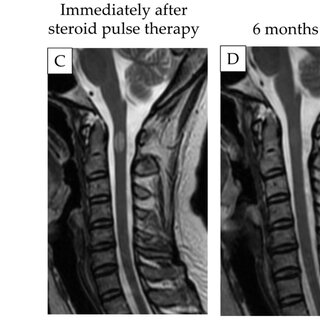

- MRIでは**頸髄または胸髄に限局した高信号域(T2強調像)**を認める。

- 治療後に病変が縮小・消失する例が多い。

| ステロイドパルス療法 | 多くの症例で速やかに症状改善。ただし再発する例もある。 |